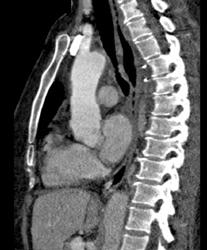

Diagnosis

Axillary Arteries